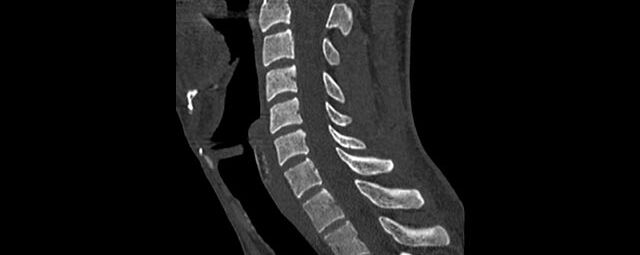

Wirbelsäule

• Darstellung von Frakturen, Tumoren und Bandscheibenveränderungen